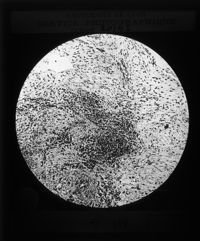

Image[Plaque diapositive. Tissus bucco-dentaires.]